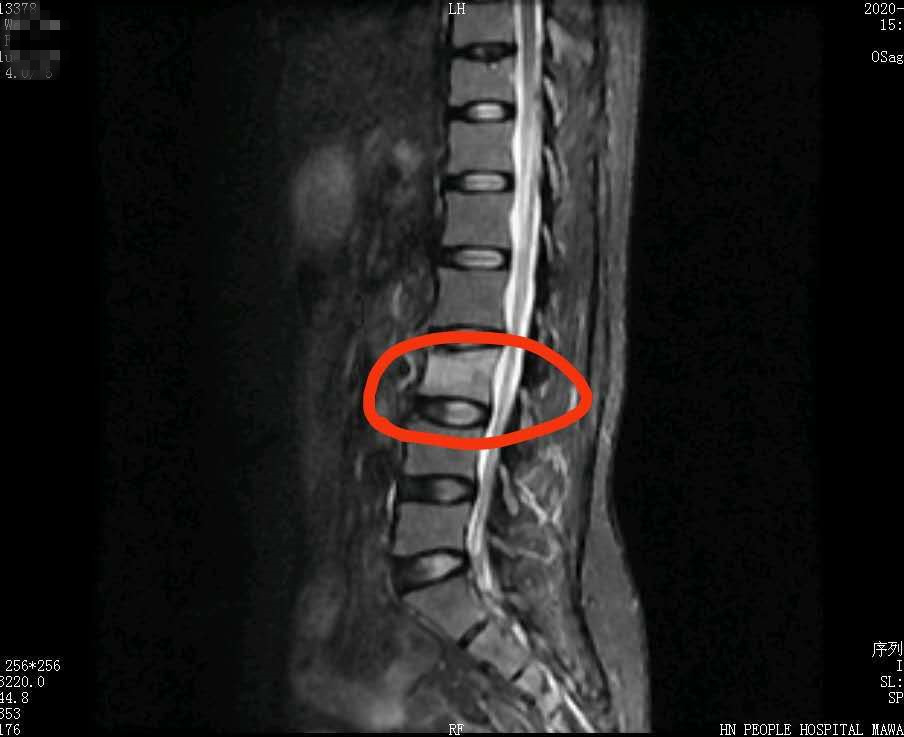

CT结果中被压缩的椎体

长沙49岁的韦女士几天前参加了社区组织的拔河比赛,由于用力过猛摔倒在地,当时腰背部就有些疼痛,但她并未在意,没想到随后的几天腰背部疼痛感越来越重,到捷克论坛 马王堆院区疼痛科就诊,被诊断为L3椎体压缩性骨折和腰椎间盘突出。

怎么拔个河,就会骨折了呢?韦女士对此十分不解。疼痛科主任曹启旺告诉韦女士,这是因为人到中年以后,骨质有所疏松,而拔河比赛具有强烈的团队对抗性,对骨骼状况、肌力、身体平衡能力有较高要求,容易造成骨骼、肌肉等身体方面损伤,而韦女士存在低骨量、轻度贫血,剧烈运动导致相邻的两节疏松的椎体被压缩发生骨折,导致疼痛。韦女士接受了经皮椎体后凸成形术,术后一天她就能下地活动,腰背部疼痛明显减轻,于6月18日出院。